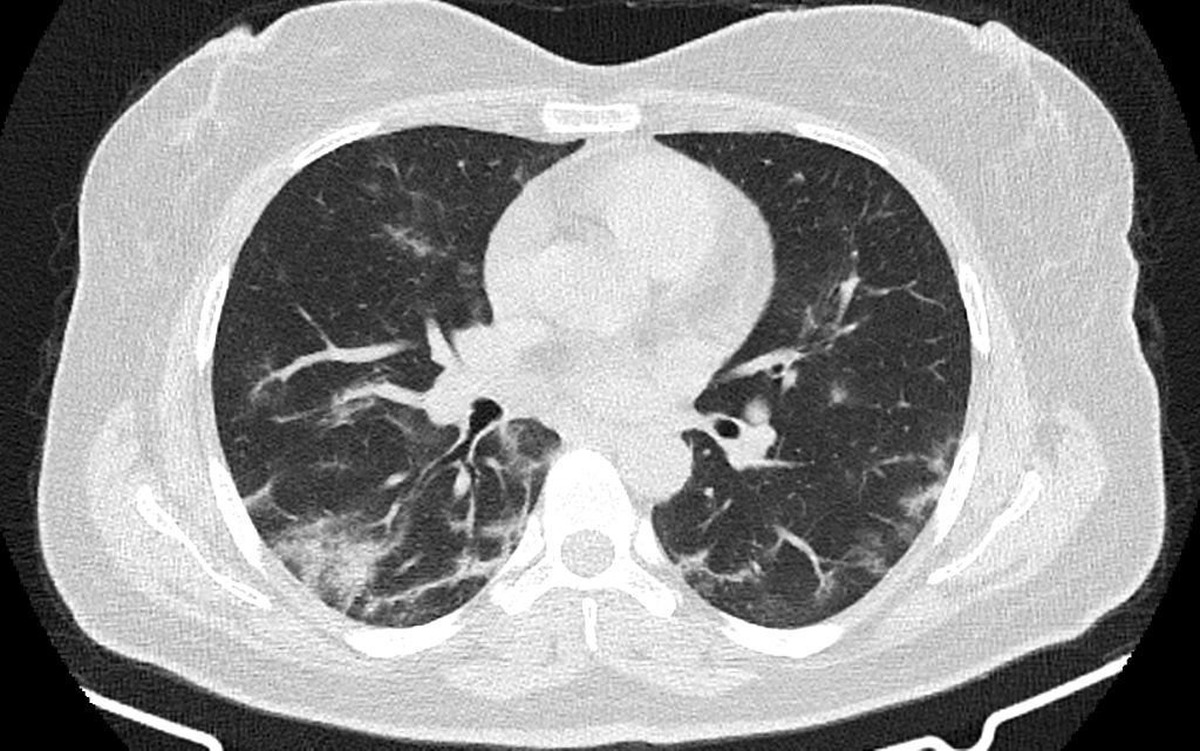

دانشمندان دانشگاه ساسکاچوان در کانادا موفق به توسعه مدل سه‌بعدی از بافت ریه شده‌اند که با سلول‌های زنده ساخته شده است. این فناوری می‌تواند تحولی در پیشگیری و درمان بیماری‌های ریوی ایجاد کند و در آینده، امکان تولید ریه‌های قابل پیوند در آزمایشگاه را نیز فراهم سازد.

تا امروز، بیشتر تحقیقات درباره بیماری‌های ریوی مانند سل، کووید-۱۹، آسم، COPD و فیبروز ریوی با استفاده از مدل‌های دوبعدی سلولی یا مدل‌های حیوانی انجام می‌شد اما این مدل‌ها محدودیت‌های جدی دارند: آنها قادر نیستند شکل و رفتار واقعی ریه‌های انسان را دقیقا شبیه‌سازی کنند.

نیراج دار، همکار این پژوهش، می‌گوید: «ریه‌های سه‌بعدی چاپ‌شده به ما کمک می‌کنند تا بیماری‌هایی مانند سل، کووید-۱۹، آسم، COPD و فیبروز ریوی را بهتر درک کنیم.» تیم پژوهشی در حال حاضر از این مدل برای مطالعه عفونت‌های مختلف تنفسی استفاده می‌کند.ریه‌ها دارای یک چارچوب ساختاری به نام ماتریکس خارج سلولی هستند که محل زندگی سلول‌های ریه محسوب می‌شود. پژوهشگران مدل‌های سه‌بعدی خود را با استفاده از بیوانک‌ها ساخته‌اند؛ موادی که شامل سلول‌های زنده واقعی هستند. آنها این مدل‌ها را با استفاده از پرتوهای الکترومغناطیسی مرکز بررسی کردند تا شکل و عملکرد بافت را بدون آسیب به نمونه‌ها تحلیل کنند.